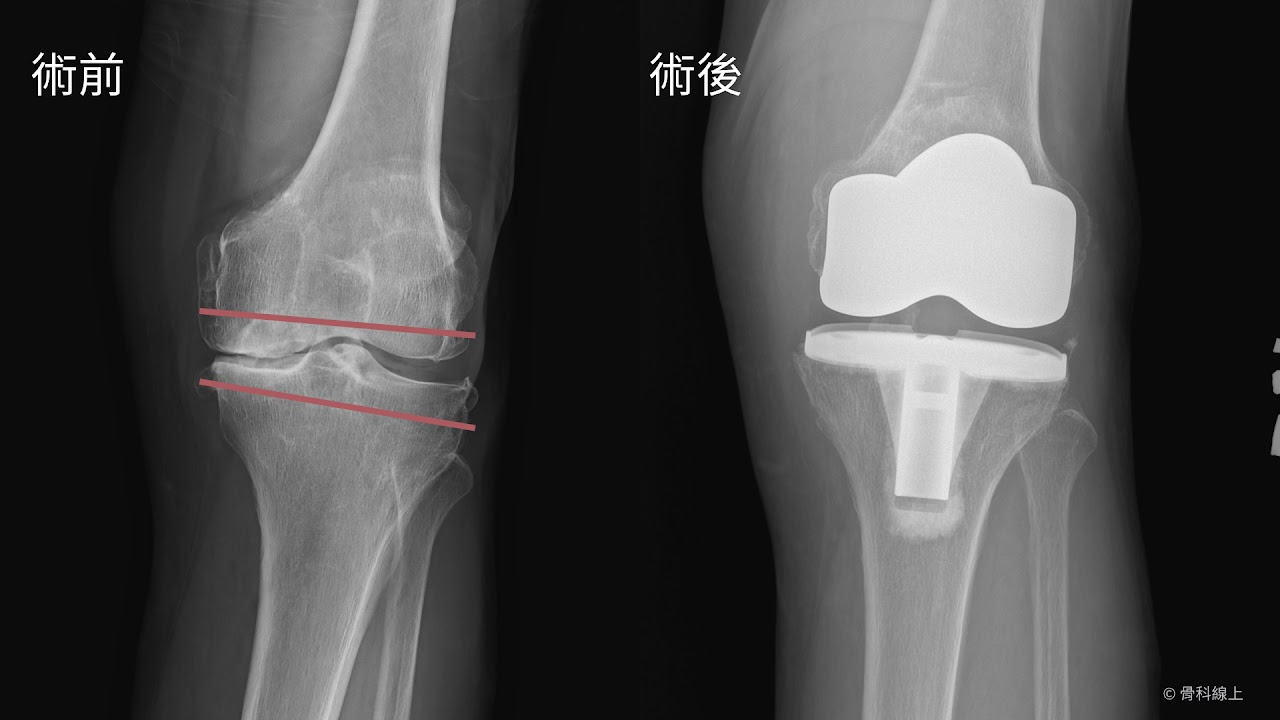

人工膝關節術前後 X 光

紅線為手術前預計要裁切的骨頭厚度,有正確的手術前計畫和手術中步驟執行,就能達到正確的手術後膝關節角度和完善的鬆緊穩定度。